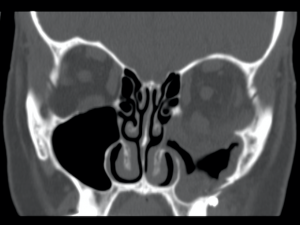

Isolated orbital floor fracture.

Diagnostic procedures

Patients suspected of suffering an orbital floor fracture should undergo thin cut (1.0 - 1.5mm) axial CT scans of the orbit with coronal reconstruction (Thin cut coronal reconstructions are actually preferred to direct coronal images as they avoid artifact from dental amalgam). In the great majority of floor fractures, a fracture can be localized above, or just medial to, the course of the infraorbital nerve. A fracture in this location leads either to a “trap door” displacement of the orbital floor, or, if a second fracture is present at the junction of the floor and medial wall, to a completely depressed, separate bony fragment. These deformities are best appreciated on coronal images. Herniation of the inferior rectus muscle into the maxillary sinus through the orbital defect does not predict clinical dysmotility. Many patients with radiologic evidence of inferior rectus herniation do not have clinical entrapment, while many patients in whom orbital fat herniates into the defect, but where the inferior rectus muscle remains in the orbit, have severe dysmotility. The extraocular muscles are connected to each other and to the orbital fat through a complicated interconnecting web of septa, such that even if fat alone is incorporated into the fracture, profound dysmotility may result. Entrapment is a purely clinical diagnosis, not a radiologic one. Rarely, if ever, is performing a forced duction test necessary or informative in making the diagnosis of extraocular muscle restriction in an awake patient with an orbital blowout fracture.